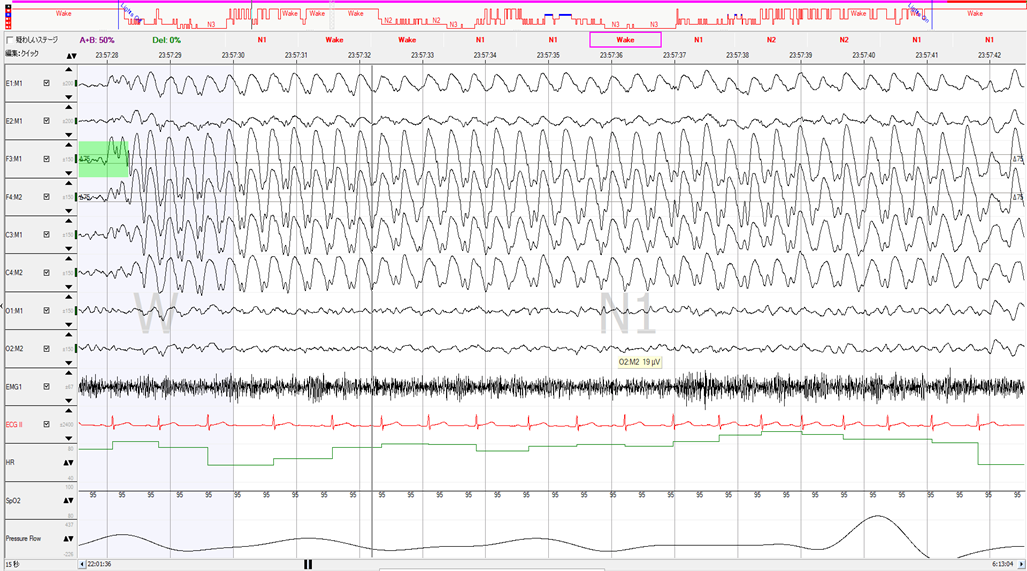

3分画面の脳波です。黒く脳波が密集している部分が棘徐波複合波形です。周期が3㎐と明確な律動性を示しており、棘波も観察されています。

15秒画面に拡大しました。感度も大きく下げています。3Hzの棘徐波複合波形であることがわかります。